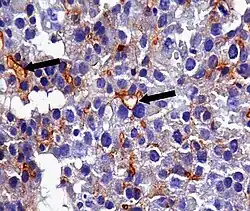

An anti-CEA antibody is an antibody against CEA. Such antibodies to CEA are commonly used in immunohistochemistry to identify cells expressing the glycoprotein in tissue samples. In adults, CEA is primarily expressed in cells of tumors (some malignant, some benign) [19] but they are particularly associated with the adenocarcinomas, such as those arising in the colon, lung, breast, stomach, or pancreas. It can therefore be used to distinguish between these and other similar cancers. For example, it can help to distinguish between adenocarcinoma of the lung and mesothelioma, a different type of lung cancer which is not normally CEA positive. Because even monoclonal antibodies to CEA tend to have some degree of cross-reactivity, occasionally giving false positive results, it is commonly employed in combination with other immunohistochemistry tests, such as those for BerEp4, WT1, and calretinin.[20] For cancers that highly express CEA, targeting CEA through radioimmunotherapy is one of the therapy approaches.[21] Engineered antibodies such as single-chain Fv antibodies (sFvs) or bispecific antibodies have been used for targeting and therapy of CEA expressing tumors both in vitro and in vivo with promising results [22][23] Regions of high CEA levels in the body can be detected with the monoclonal antibody arcitumomab.[24]